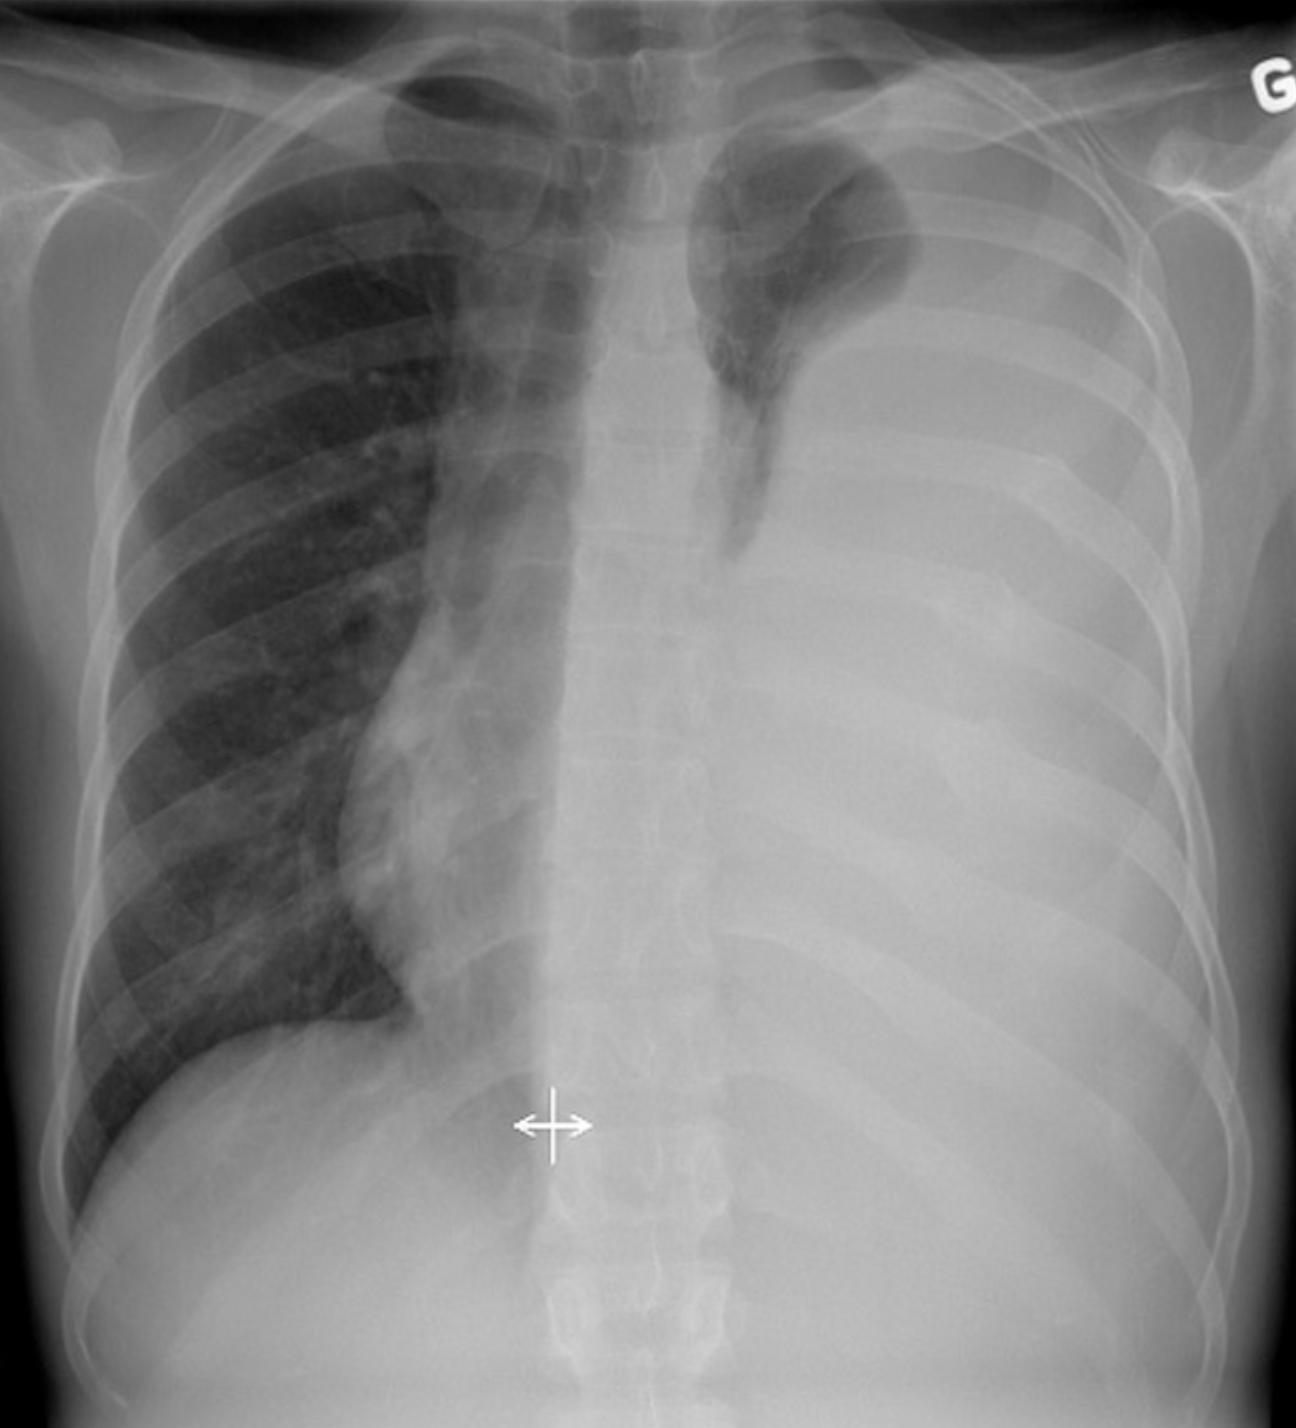

Une femme de 52 ans consulte pour de la toux persistante depuis plus d’un mois. Cette toux l’empêche de dormir dans son lit et elle dort maintenant assise sur le fauteuil du salon afin d’être plus confortable. La dame se dit très fatiguée. Par ailleurs, la patiente ne rapporte pas d’infection des voies respiratoires récentes ou de problèmes digestifs. La patiente n’a jamais fumé et ne prend pas de médications sur une base régulière. Elle dit que la prise de sirop antitussif n’aide pas à diminuer ses symptômes.

Dans le contexte de toux subaigüe sans diagnostic clinique précis, une radiographie pulmonaire est demandée. Quelle est la meilleure interprétation de la radiographie?

A

Métastases pulmonaires diffuses